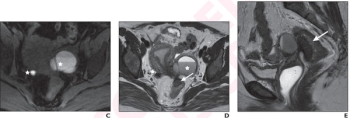

MRI or Ultrasound for Evaluating Pelvic Endometriosis?: Seven Takeaways from a New Literature Review

While noting the strength of MRI for complete staging of disease and ultrasound’s ability to provide local disease characterization, the authors of a new literature review suggest the two modalities offer comparable results for diagnosing pelvic endometriosis.